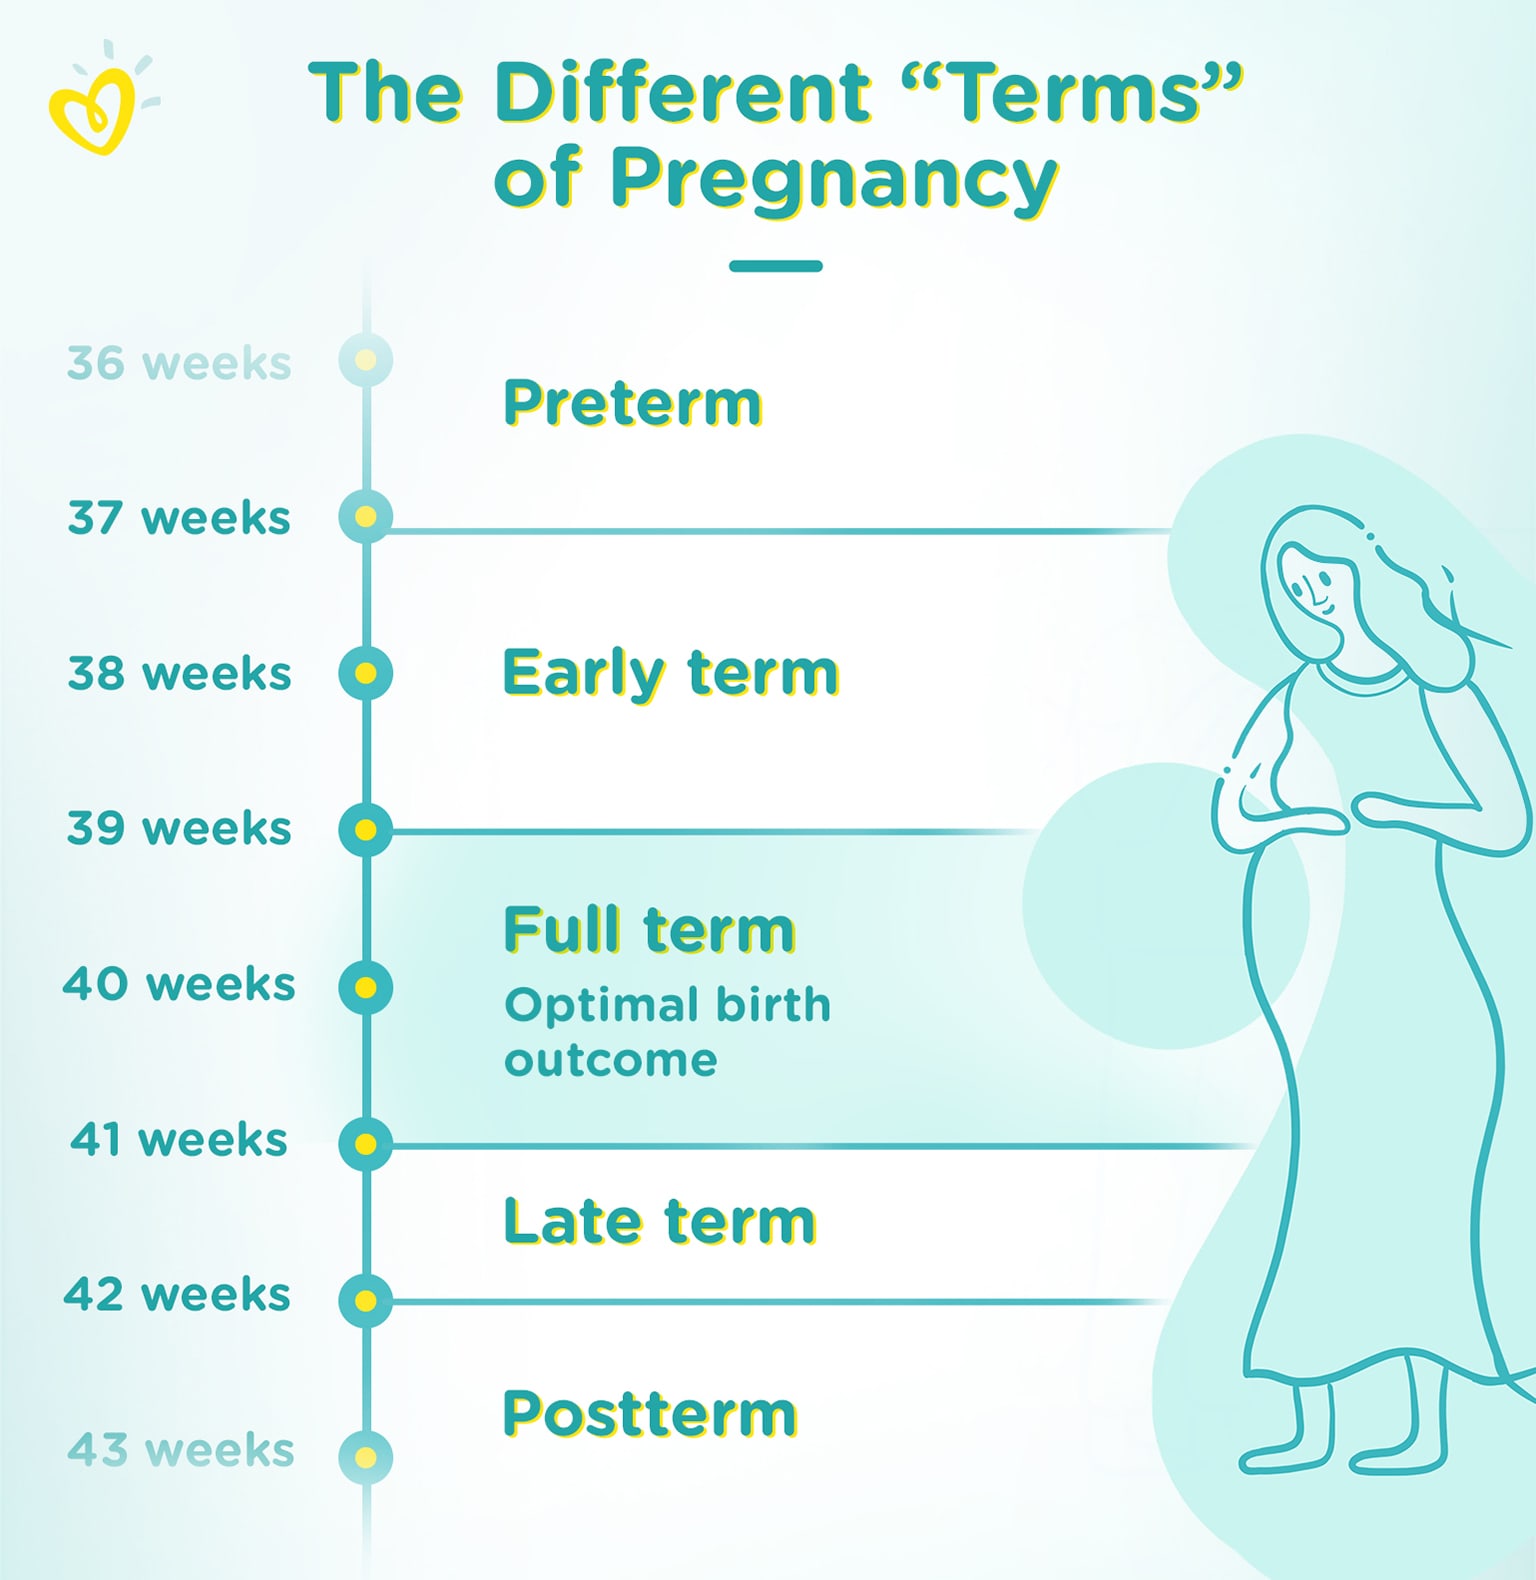

Doctors To Pregnant Women: Wait At Least 39 Weeks | WBUR

Full Term Pregnancy 36 Weeks / Quick Answer Is Baby Fully Developed At …

Full Term Pregnancy 36 Weeks / Quick Answer Is Baby Fully Developed At …